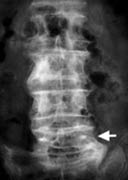

腰椎因骨質疏鬆被壓迫變形